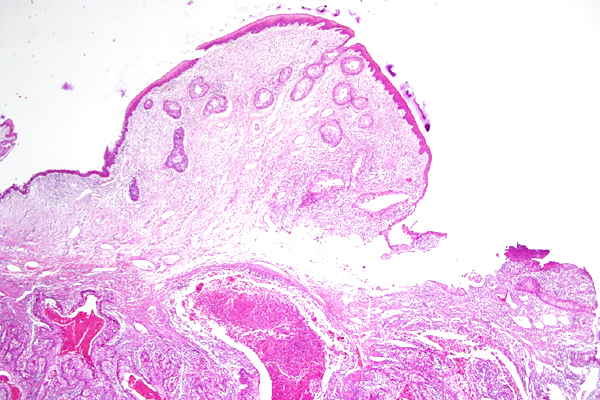

| 2x   |   Hematoxylin and Eosin | ||||

The superficial subconjunctival connective tissue is expanded by clear space (edema).